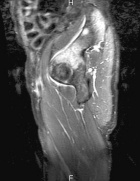

D.R. - 65 year old male, c/o worsening right hip/buttock pain for six months. Pain is constant, worse with activity. Tylenol helps a bit. No F/C or constitutional sx.

PMH: Crohn's disease, nephrolithiasis, prostate infection, gallstones

Zoom image: Radiological image Radiological image.